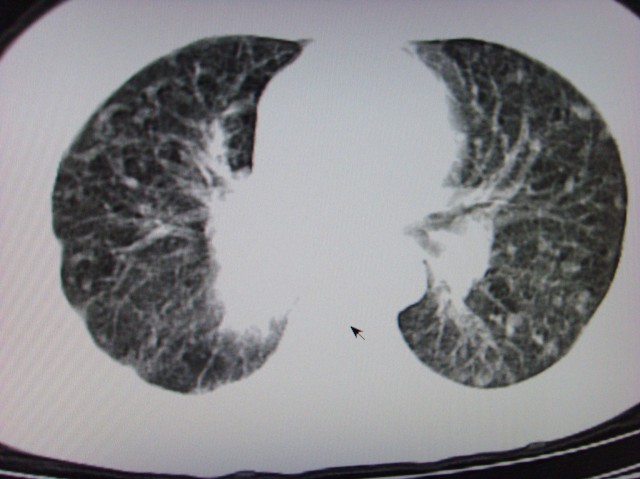

还有肺不张

中央型肺癌伴阻塞性肺炎

经典病历,肿块。肺内转移、淋巴结转移。胸膜仗义